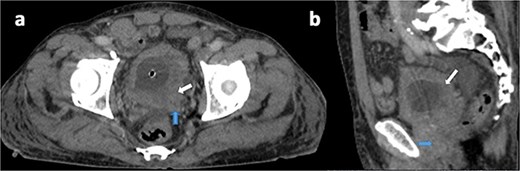

A 75-year-old male with no known history of NF-1 presented with hematuria and urinary obstruction for 3 months. Contrast-enhanced CT imaging revealed a heterogeneous mass measuring 6.5 × 4 × 2 cm with irregular borders and central necrosis, extending into the perivesical fat and abutting the prostate (Fig. 1).

Axial (a) and sagittal (b) contrast-enhanced CT views in portal phase showing a diffuse and irregular thickening of bladder wall, pronounced on the left posterolateral side (white arrow), with invasion of the seminal vesicles and the prostate (blue arrow).